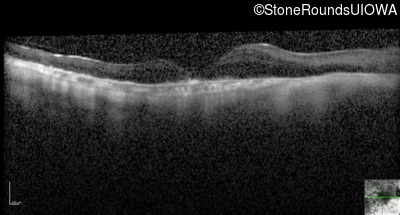

Optical Coherence Tomography - Right - 20/250

Exemplar / OCT Stack

OCT Stack